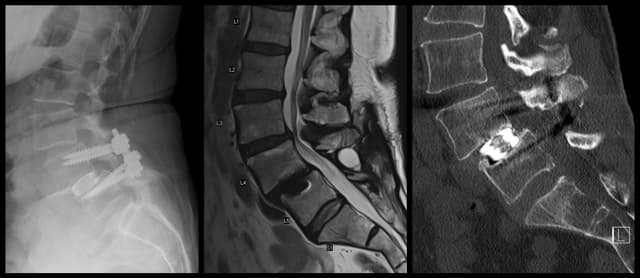

L3-4 TLIF

Imaging

Pre-op

Post-op